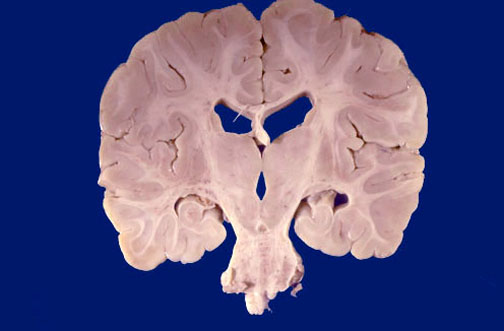

Identify the following regions of the normal brain by clicking in the image below:

Pons - Thalamus - Fornix - Hippocampus